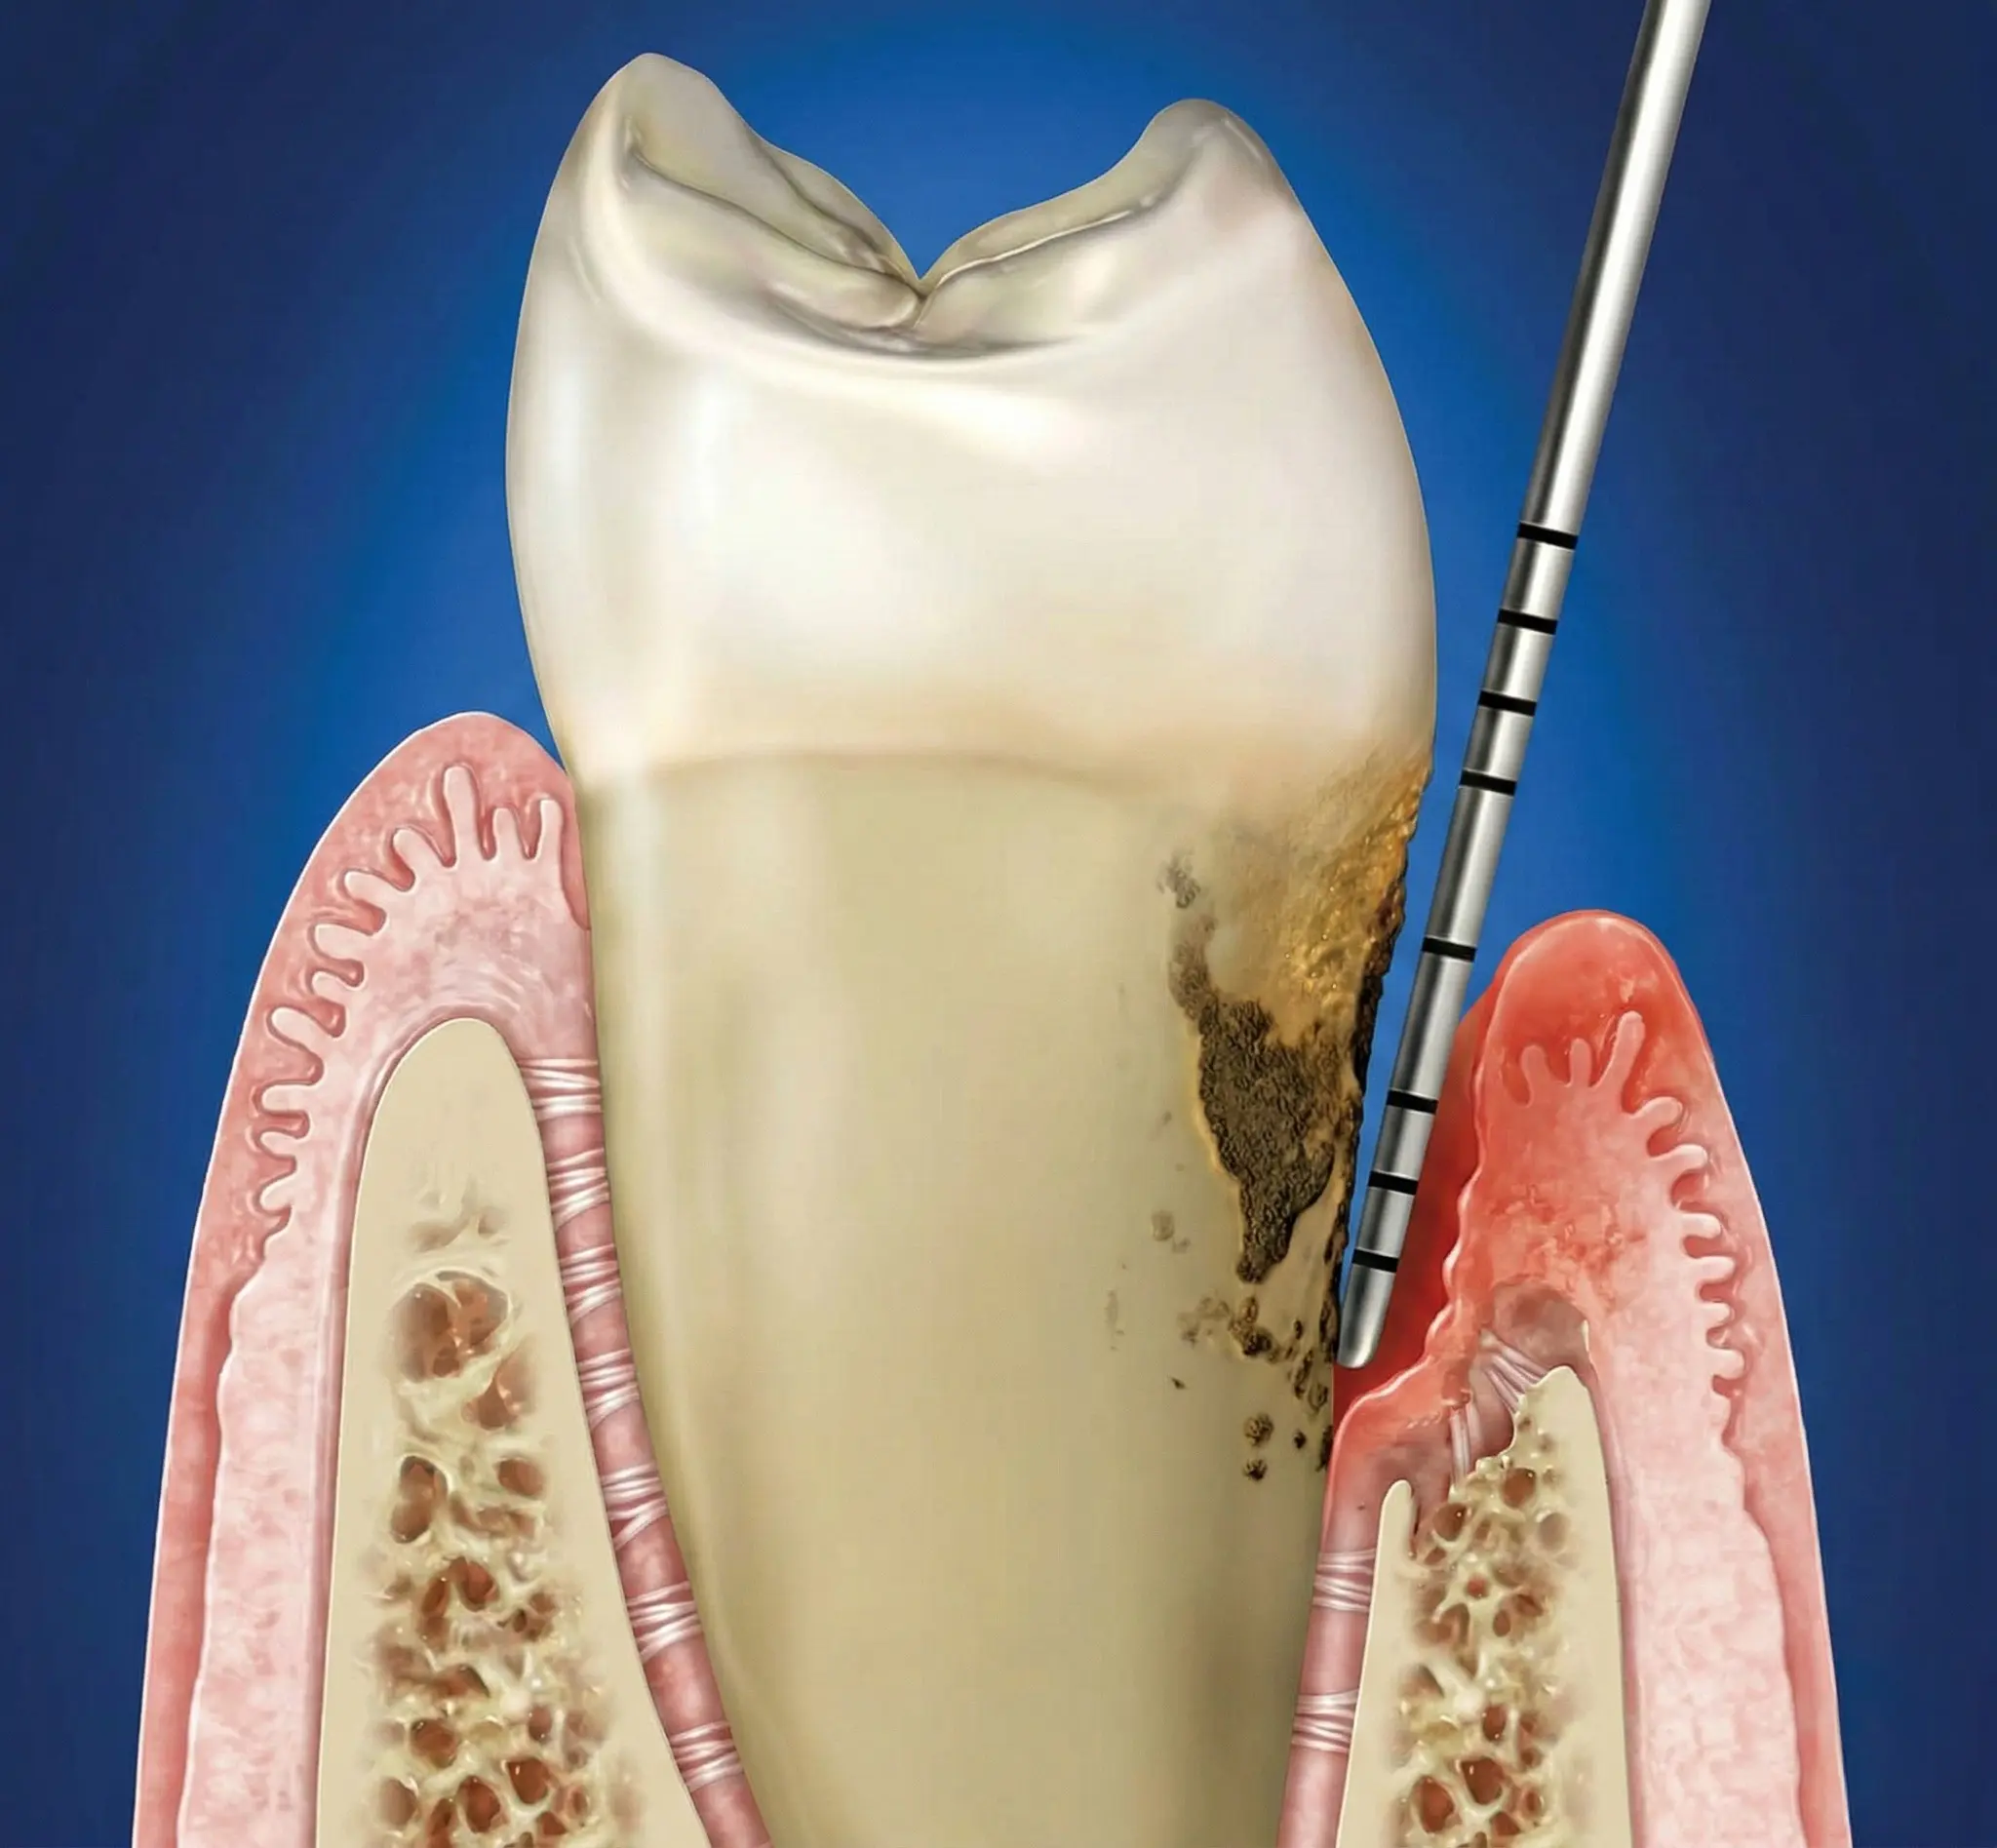

Parodontite stadio III e IV: diagnosi, terapia causale, chirurgia rigenerativa. Come funziona il trattamento passo per passo, con evidenze scientifiche.

Perché le gengive si ritirano, quando preoccuparsi e cosa può fare il parodontologo. Classificazione di Cairo, innesto connettivale, lembo coronale.

Piorrea è il nome popolare della parodontite, superato da decenni. Cosa significa, come si diagnostica e come si cura oggi secondo le linee guida EFP.